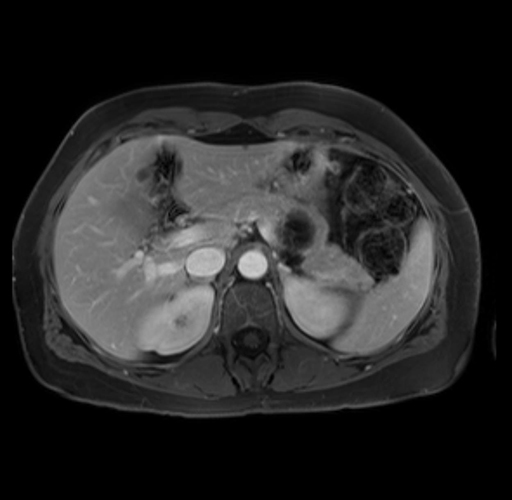

Imaging Analysis

Look through the patient's CT scan to identify any areas of concern for the necessary procedure.

Based on your CT findings, which issue(s) are present and would give reason for "planned slowing down moment(s)" in this case?